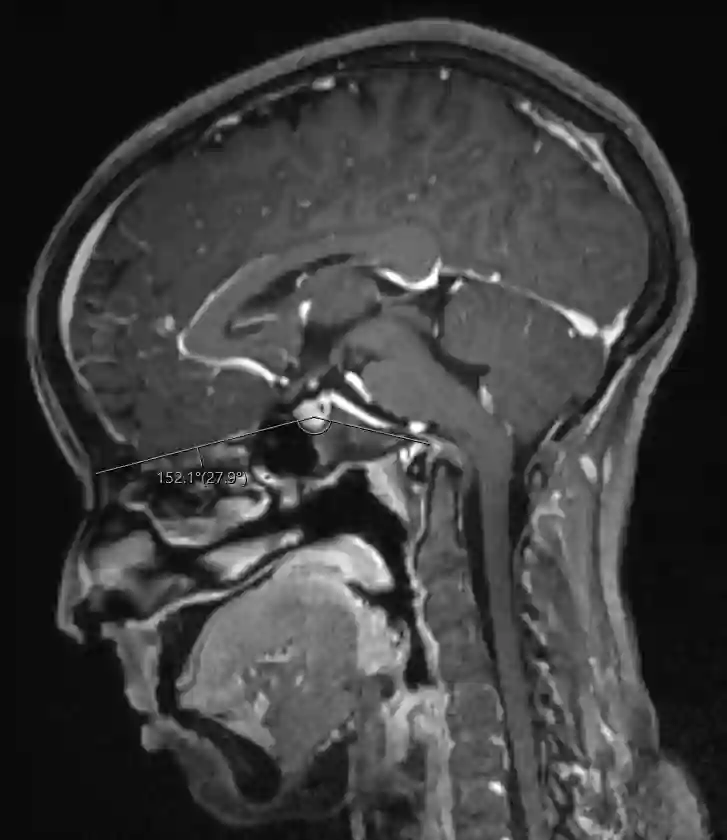

MRT Platybasie

MRT Abbildung eines Patienten mit einer Platybasie und abgemessenem Winkel.